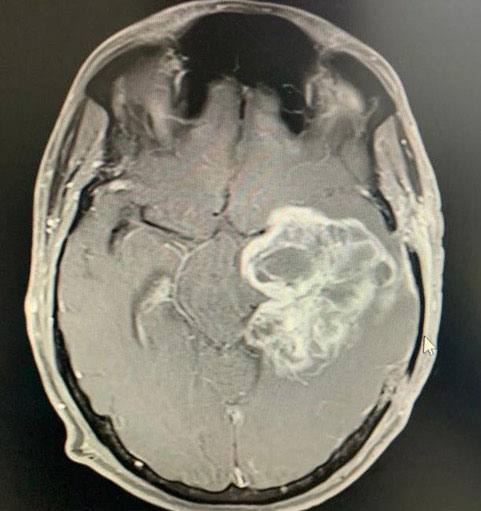

Dr. Ujwal Yeole is an experienced neurosurgeon specializes in treating a wide spectrum of neurological conditions including neuro-oncology, peripheral nerve disorders, vascular disorders, spinal pathologies, pediatric neurosurgery, neuro-trauma and skull base neuroendoscopic procedures.